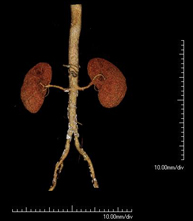

- Angio-TC aorta abdominal  Prueba diagnóstica no invasiva que consiste en el estudio de la arteria aorta abdominal obteniendo imágenes de alta definición anatómica mediante el empleo de un equipo de TC (Tomografía Computarizada) y de contraste yodado. La calidad de las imágenes permite realizar reconstrucciones en 2D y 3D gracias a estaciones de trabajo especializadas en el estudio arterial. Está indicado en aquellos pacientes con enfermedad vascular (aterosclerosis), en aneurismas de aorta, en pacientes con dolor abdominal de posible origen vascular, en estudios pre-quirúrgicos de lesiones adyacentes a la aorta abdominal como "mapa" vascular, etc. La información obtenida de forma no invasiva es indispensable para los pacientes que requieren tratamiento percutáneo o quirúrgico. En aquellos pacientes que solo requieren un seguimiento de las lesiones vasculares, esta técnica es la técnica no invasiva de elección junto con la angio-RM. Prueba diagnóstica no invasiva que consiste en el estudio de la arteria aorta abdominal obteniendo imágenes de alta definición anatómica mediante el empleo de un equipo de TC (Tomografía Computarizada) y de contraste yodado. La calidad de las imágenes permite realizar reconstrucciones en 2D y 3D gracias a estaciones de trabajo especializadas en el estudio arterial. Está indicado en aquellos pacientes con enfermedad vascular (aterosclerosis), en aneurismas de aorta, en pacientes con dolor abdominal de posible origen vascular, en estudios pre-quirúrgicos de lesiones adyacentes a la aorta abdominal como "mapa" vascular, etc. La información obtenida de forma no invasiva es indispensable para los pacientes que requieren tratamiento percutáneo o quirúrgico. En aquellos pacientes que solo requieren un seguimiento de las lesiones vasculares, esta técnica es la técnica no invasiva de elección junto con la angio-RM.

- Angio-TC arterias renales  Prueba diagnóstica no invasiva que consiste en el estudio de las arterias renales obteniendo imágenes de alta definición anatómica mediante el empleo de un equipo de TC (Tomografía Computarizada) y de contraste yodado. La calidad de las imágenes permite realizar reconstrucciones en 2D y 3D gracias a estaciones de trabajo especializadas en el estudio arterial. Esta prueba está indicada, por ejemplo, en aquellos pacientes que sufren de HTA refractaria al tratamiento, en pacientes con lesiones renales para tener un mapa "vascular" pre-quirúrgico, etc. Prueba diagnóstica no invasiva que consiste en el estudio de las arterias renales obteniendo imágenes de alta definición anatómica mediante el empleo de un equipo de TC (Tomografía Computarizada) y de contraste yodado. La calidad de las imágenes permite realizar reconstrucciones en 2D y 3D gracias a estaciones de trabajo especializadas en el estudio arterial. Esta prueba está indicada, por ejemplo, en aquellos pacientes que sufren de HTA refractaria al tratamiento, en pacientes con lesiones renales para tener un mapa "vascular" pre-quirúrgico, etc.

- Angio-TC aorto-ilíaco Prueba diagnóstica no invasiva que consiste en el estudio de las arterias ilíacas y la aorta abdominal obteniendo imágenes de alta definición anatómica mediante el empleo de un equipo de TC (Tomografía Computarizada) y de contraste yodado. La calidad de las imágenes permite realizar reconstrucciones en 2D y 3D gracias a estaciones de trabajo especializadas en el estudio arterial. Esta prueba está especialmente indicada como estudio pre-quirúrgico (mapa vascular) antes de intervenciones percutáneas o quirúrgicas de aorta abdominal, como el estudio complementario en pacientes con isquemia de miembros inferiores, etc. Prueba diagnóstica no invasiva que consiste en el estudio de las arterias ilíacas y la aorta abdominal obteniendo imágenes de alta definición anatómica mediante el empleo de un equipo de TC (Tomografía Computarizada) y de contraste yodado. La calidad de las imágenes permite realizar reconstrucciones en 2D y 3D gracias a estaciones de trabajo especializadas en el estudio arterial. Esta prueba está especialmente indicada como estudio pre-quirúrgico (mapa vascular) antes de intervenciones percutáneas o quirúrgicas de aorta abdominal, como el estudio complementario en pacientes con isquemia de miembros inferiores, etc.

- Angio TC d'aorta abdominal Prova diagnòstica no invasiva que consisteix en l'estudi de l'artèria aorta abdominal amb l'obtenció d'imatges d'alta definició anatòmica mitjançant l'ús d'un equip de TC (Tomografia Computaritzada) i contrast iodat. La qualitat de les imatges permet realitzar reconstruccions en 2D i 3D gràcies a estacions de treball especialitzades en l'estudi arterial. Està indicat en aquells pacients que pateixen malaltia vascular (arteriosclerosi), aneurismes d'aorta, en pacient amb dolor abdominal d'un possible origen vascular, en estudis prequirúrgics de lesions adjacents a l'aorta abdominal com el "mapa" vascular, etc. La informació obtinguda de forma no invasiva és indispensable per als pacients que requereixen tractament percutani o quirúrgic. En aquells pacients que només requereixen un seguiment de les lesions vasculars, aquesta tècnica és la tècnica no invasiva d'elecció juntament amb l'angio RM. Prova diagnòstica no invasiva que consisteix en l'estudi de l'artèria aorta abdominal amb l'obtenció d'imatges d'alta definició anatòmica mitjançant l'ús d'un equip de TC (Tomografia Computaritzada) i contrast iodat. La qualitat de les imatges permet realitzar reconstruccions en 2D i 3D gràcies a estacions de treball especialitzades en l'estudi arterial. Està indicat en aquells pacients que pateixen malaltia vascular (arteriosclerosi), aneurismes d'aorta, en pacient amb dolor abdominal d'un possible origen vascular, en estudis prequirúrgics de lesions adjacents a l'aorta abdominal com el "mapa" vascular, etc. La informació obtinguda de forma no invasiva és indispensable per als pacients que requereixen tractament percutani o quirúrgic. En aquells pacients que només requereixen un seguiment de les lesions vasculars, aquesta tècnica és la tècnica no invasiva d'elecció juntament amb l'angio RM.

- Angio TC d'artèries renals Prova diagnòstica no invasiva que consisteix en l'estudi de les artèries renals amb l'obtenció d'imatges d'alta definició anatòmica mitjançant l'ús d'un equip de TC (Tomografia Computaritzada) i contrast iodat. La qualitat de les imatges permet realitzar reconstruccions en 2D i 3D gràcies a estacions de treball especialitzades en l'estudi arterial. Aquesta prova està indicat en aquells pacients que pateixen HTA refractària al tractament, en pacients amb lesions renals que tenen un mapa vascular prequirúrgic, etc. Prova diagnòstica no invasiva que consisteix en l'estudi de les artèries renals amb l'obtenció d'imatges d'alta definició anatòmica mitjançant l'ús d'un equip de TC (Tomografia Computaritzada) i contrast iodat. La qualitat de les imatges permet realitzar reconstruccions en 2D i 3D gràcies a estacions de treball especialitzades en l'estudi arterial. Aquesta prova està indicat en aquells pacients que pateixen HTA refractària al tractament, en pacients amb lesions renals que tenen un mapa vascular prequirúrgic, etc.

- Angio TC d'aorta-ilíaca Prova diagnòstica no invasiva que consisteix en l'estudi de les artèries ilíaques i l'aorta abdominal amb l'obtenció d'imatges d'alta definició anatòmica mitjançant l'ús d'un equip de TC (Tomografia Computaritzada) i contrast iodat. La qualitat de les imatges permet realitzar reconstruccions en 2D i 3D gràcies a estacions de treball especialitzades en l'estudi arterial. Aquesta prova està especialment indicada com a estudi prequirúrgic (mapa vascular) abans d'intervencions percutànies o quirúrgiques d'aorta abdominal, estudi complementari en pacients amb isquèmia de membres inferiors, etc. Prova diagnòstica no invasiva que consisteix en l'estudi de les artèries ilíaques i l'aorta abdominal amb l'obtenció d'imatges d'alta definició anatòmica mitjançant l'ús d'un equip de TC (Tomografia Computaritzada) i contrast iodat. La qualitat de les imatges permet realitzar reconstruccions en 2D i 3D gràcies a estacions de treball especialitzades en l'estudi arterial. Aquesta prova està especialment indicada com a estudi prequirúrgic (mapa vascular) abans d'intervencions percutànies o quirúrgiques d'aorta abdominal, estudi complementari en pacients amb isquèmia de membres inferiors, etc.